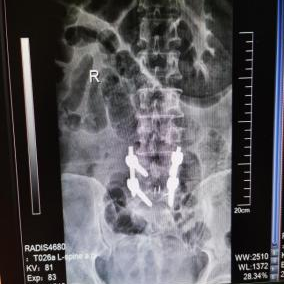

2025年11月1日,由遵义市医学会手外科分会主办、遵义市第二城市医疗集团(贵州航天医院)承办的遵义市医学会手外科分会学术交流会暨贵州省继续医学教育项目《急诊手外伤治疗临床研究新进展专题研讨班》在贵州航天医院成功举办,汇聚了遵义市手外科领域专家及基层医疗骨干,通过专题研讨与临床经验分享,共探急诊手外伤诊疗新进展。 会议特邀遵义市医学会手外科分会主任委员金文虎教授,遵义市医学会手外科分会副主任委员张子阳教授,遵义市医学会手外科分会常务委员杨绍浦教授,贵州航天医院陈明勇教授、赵兴东教授等遵义市手外伤专家进行交流分享;贵州航天医院党委委员、副院长彭亮参加会议并致辞,贵州航天医院骨科医务人员,遵义市第二城市医疗集团成员单位及红花岗区、绥阳县、桐梓县等区县医疗机构手外伤骨干参与。 贵州航天医院党委委员、副院长彭亮致辞 学术交流 本次学术交流以“急诊手外伤治疗临床研究新进展”为主题,通过理论授课与临床案例结合,共同探讨急诊手外伤临床诊疗全链条诊疗策略、关键技术、临床研究新进展,促进规范化诊疗技术向基层下沉,助力提升区域手外伤应急处置与修复能力。 贵州航天医院赵兴东教授分享《急诊手外伤的诊断与治疗原则》 贵州航天医院陈明勇教授分享《开放性骨折的治疗原则》 贵州航天医院张军教授分享《甲沟炎Winograd手术的临床应用》 贵州航天医院赵兴东教授分享《手部常见的皮肤缺损及治疗原则》 贵州航天医院张艳金教授分享《开放性骨折的清创术》 贵州航天医院冷家雄教授分享《下肢创面修复的常用皮瓣之股前外侧皮瓣》 贵州航天医院邬夏荣教授分享《踝关节慢性不稳的诊治》 贵州航天医院卢懿明教授分享《掌骨骨折》 贵州航天医院张艳金教授分享《手部肌腱的解剖与修复方法》 本次研讨班为遵义市手外科领域医务人员提供了深度交流契机,强化了医疗机构间的协作网络,进一步推动学科创新与临床实践融合,为健康遵义建设注入新动能。 贵州航天医院骨科专家简介 陈明勇 骨一科主任,副主任医师 临床擅长:从事创伤骨科工作约20年,对骨缺损、骨不连、骨肿瘤、肢体畸形等的肢体矫形重建及功能重建,慢性化脓性骨髓炎的根治治疗、糖尿病足的保肢治疗、快速康复理念(ERAS)下的老年骨折的诊治,四肢复杂骨折的诊治,四肢骨折等微创手术治疗具有丰富的临床经验。 2004年毕业于遵义医学院临床专业,曾在中国人民解放军总医院、广西医科大学第一附属医院、上海第六人民医院骨科进修。中国中西医结合学会骨伤科专业委员会横向骨搬移治疗糖尿病足及微血管网再生学组首届委员,遵义市医学会创伤分会常务委员。 瞿 晖 骨科党支部书记,骨二科主任,副主任医师 临床擅长:对骨科的常见病、关节外科、脊柱外科及运动医学疾病的诊治具有丰富的临床经验,熟练掌握骨科手术操作技术。 毕业于遵义医学院临床医学系,2005年前往广州中山大学第一附院骨显微医学部进修学习,2011年前往成都华西医院进修学习,并多次在省内外学习骨科相关知识,是中华医学会骨科分会会员。 赵小锋 中共党员,骨二科副主任,副主任医师 临床擅长:从事骨科临床工作11年,对骨科常见病、多发病诊疗有较为丰富的临床经验,擅长脊柱相关疾病诊断及治疗,尤其是颈、腰、腿疼痛疾病诊断及治疗,擅长胸腰椎骨折微创经皮穿刺内固定术、经皮穿刺椎体成形术、经皮穿刺脊柱内镜下腰椎间盘摘除术、单纯开创腰椎间盘摘除术、腰椎滑脱复位椎间植骨椎融合内固定术、腰椎管狭窄减压融合内固定术及人工髋、膝关节置换术等。 2012年毕业于遵义医学院外科学专业硕士研究生,2019年参加“遵义市115医学人才精英计划”于上海交通大学第一附属医院培训学习,2023年于北京大学第三人民医院脊柱外科进修学习,曾获得遵义市优秀医师荣誉称号。 遵义市手外科第一届委员,遵义市医学会创伤分会第一届委员,遵义市医学会创伤分会第二届委员,贵州省康复医学会第三届脊柱脊髓专业会委员,遵义市医学会烧伤与整形外科学分会委员,发表论文5篇,其中国家级核心期刊1篇,SCI论文1篇,主持市级课题1项并结题,参与市级课题2项。 赵兴东 骨科主任医师 临床擅长:擅长骨科的常见病及各种创伤、四肢骨折创伤修复、骨感染、手足疾病的诊治和手足体表畸形的矫形整复,熟练掌握骨科四肢骨病及创伤的手术操作技术,尤其在四肢关节复杂性损伤、手足外伤、组织缺损创面、难治创面的皮瓣修复方面及平足、高弓足矫形方面及四肢慢性疼痛诊治、康复方面具有丰富的临床经验。 硕士研究生,毕业于遵义医学院临床外科系,2015年前往山东省立医院手足外科进修学习;遵义市医学分会创伤分会第一、二届委员,遵义市手外科医学会第二委届员会常务委员;在省级及省级以上期刊发表文章9篇,参编著作2部,参与主持并完成市级课题1项,参与市级课题2项、省级课题1项。 张艳金 中共党员,骨科副主任医师 临床擅长:从事骨外科工作16年,对复合伤、多发伤的救治、四肢骨干骨折、关节周围骨折、骨肿瘤、骨髓炎等诊治具有丰富的临床经验。 中共党员,硕士研究生,2006年本科毕业于山西医科大学第二临床医学院,2011年研究生毕业于北京军区总医院;在“老年COPD患者合并髋部骨折的诊治”国际合作课题组研究两年,在老年髋部骨折的诊治方面具有丰富的经验,并发表论文6篇;主持遵义市级课题1项,承担遵义医科大学的临床教学工作,获得遵义医科大学优秀带教老师荣誉。编撰有《骨科疾病诊疗精粹》一书,开展2项新技术,编撰地方规范《务川自治县创伤骨科常见疾病诊疗规范》一书。 张俊凯 骨科副主任医师 临床擅长:从事骨科临床工作28年,对创伤骨折、骨感染、骨缺损、骨不连等外科诊治,四肢骨折的微创手术治疗,四肢复杂骨折(如关节内粉碎性骨折、多发骨折等)的损伤控制及手术治疗等具有丰富的临床经验。 1995年毕业于遵义医学院临床专业,2009年前往复旦大学附属医院骨科进修1年。 卢懿明 中共党员,骨科副主任医师 临床擅长:从事骨科工作18年,对创伤骨折、四肢骨折的微创手术治疗、四肢复杂骨折(如关节内粉碎性骨折、多发骨折等)的损伤控制及手术治疗,尤其是髋部骨折的PFNA等微创技术,踝关节骨折、膝关节周围骨折的Mipo微创技术等具有丰富的临床经验,开展了4项新技术,发明6项新型专利技术。 2005年毕业于遵义医学院临床专业,2017年,前往南方医科大学第三附属医院骨科进修半年,回院后运用Mipo技术对骨干骨折及干骺端骨折的治疗技术,同时积极开展骨盆骨折、髋臼骨折腹直肌外侧切口的应用;发表了多篇专业论文,经常参与省内外学术交流会授课,获得医院荣誉称号多个。 邬夏荣 骨科副主任医师 临床擅长:从事骨科工作16年,对四肢复杂骨折、骨肿瘤的诊治,尤其是足踝创伤、慢性踝关节损伤、平足症等诊疗具有丰富的临床经验。 2006年毕业于遵义医科大学临床医学专业,曾在陆军军医大学西南医院进修学习,发表多篇骨科学术论文。 余德怀 中共党员,骨科副主任医师 临床擅长:从事骨科工作10余年,对运动医学、骨关节、脊柱外科常见病、多发病的诊治具有丰富的临床经验。 硕士研究生,2011年毕业于遵义医学院临床医学专业,曾前往遵义医科大学附属医院运动医学专业进修学习;是贵州省医学会运动医学分会青年委员,西部关节镜联盟委员;发表多篇骨科学术论文。 冯 乾 骨科副主任医师 临床擅长:从事骨科工作近20年,熟练掌握骨科多发病及常见病的诊治,尤其对脊柱退变性疾病的诊断及治疗具有丰富的临床经验,主要研究脊柱微创相关治疗方式,能熟练开展椎间孔镜及UBE。 曾前往北京大学第三医院进修学习疼痛及椎间孔镜、首都医科大学友谊医院专业进修脊柱内镜;是贵州省康复医学会第三届脊柱脊髓专业委员会委员;发明专利3项、发表脊柱外科专业论文多篇。 贵州航天医院骨科简介 基本情况 贵州航天医院(原3417医院)骨科组建于1968年,前身是以创伤和断肢(断指)再植闻名于世的上海市第六人民医院骨科,中国断肢(断指)再植的奠基者、中科院院士陈仲伟等专家莅临科室指导医疗和教学,并在70年代开展了贵州省首例断肢(断指)再植手术。组建50余年来,诊治患者已逾百万,挽救了无数的伤病员,成为了保障遵义地区人民群众健康的重要支撑。 经过几代人的不懈努力,今天的骨科,已由创伤骨科发展至骨病、骨肿瘤、骨结核等领域,现有脊柱外科、关节外科、四肢创伤、手足外科四个亚专科,成为了集医疗、教学、科研于一体的综合学科,是贵州省临床重点专科、遵义市临床重点专科、遵义市骨科临床医学中心、遵义市基层骨科专科联盟理事长单位。 科室目前开放床位110张,共有医护人员50余人,副高级以上专家18人,硕士研究生15人。拥有一流骨科医疗设备多台,每年不定期选派优秀技术骨干到全国各大知名医学院校进修、学习、参观、交流,并邀请国内、国外知名专家教授来院进行交流、指导,通过不断引进国内外先进的诊疗技术,科室医疗技术水平稳步提升,为广大人民群众提供了优质的医疗服务。 专科特色 骨一科 (一)骨缺损、骨不连的肢体与功能重建 胫骨横向骨搬移技术治疗糖尿病足: (二)慢性骨髓炎的根治治疗 (三)肢体缺血性疾病如糖尿病足、脉管炎的保肢治疗 (四)皮瓣修复 (五)复杂创伤的治疗 (六)老年髋部骨折及小儿骨折快速手术 老年髋部骨折: 骨二科 (一)胸腰椎骨折微创经皮椎弓根螺钉固定术 (二)老年性骨质疏松性患者腰椎滑脱脊柱内固定术(骨水泥螺钉) (三)V形双通道脊柱内镜技术(VBE)腰椎融合术治疗腰椎退行性疾病 (四)老年性骨质疏松性骨折(PVP/PKP)术 (五)人工髋关节置换术 (六)双侧股骨头坏死人工全髋关节置换 (七)右侧全髋置换术后假体周围骨折翻修 (八)人工膝关节置换术 (九)人工膝关节假体松动翻修 (十)关节镜技术 传统手术切口 关节镜技术切口 诊疗范围 骨一科 1.四肢创伤、矫形。 2.手、足踝外科。 骨二科 End